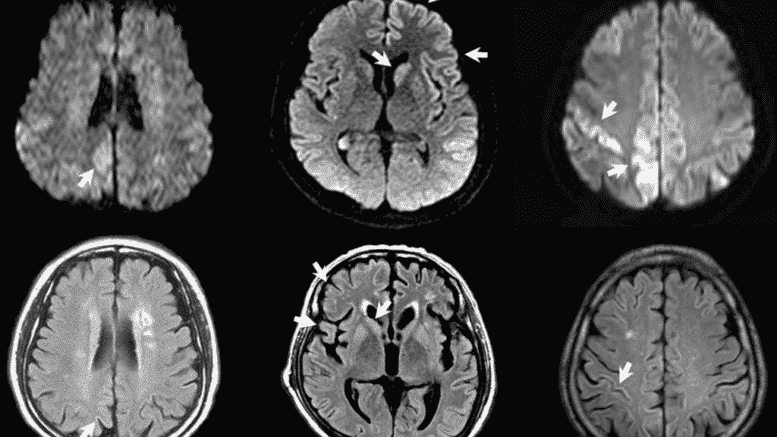

Prion disease is the animal equivalent of Bovine Spongiform Encephalopathy (BSE), or Mad Cow Disease. It destroys brain tissue, is degenerative, transmissible and fatal. As such, gene therapy shots have the potential to be a deadly bio-weapon.